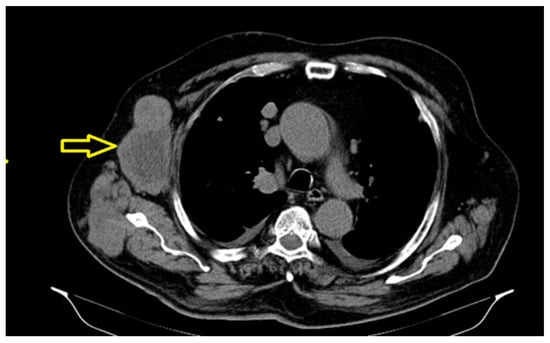

The significant dimensional progression of the right axillary tumor adenomegaly, associated with extensive central necrosis, was also determined (Figure 5), along with an osteocondensation-focused lesion centered on the left pubic branch with a suspicious aspect for secondary determination.

Figure 5. The important dimensional progression of the right axillary tumor adenomegaly, currently associated with extensive central necrosis.